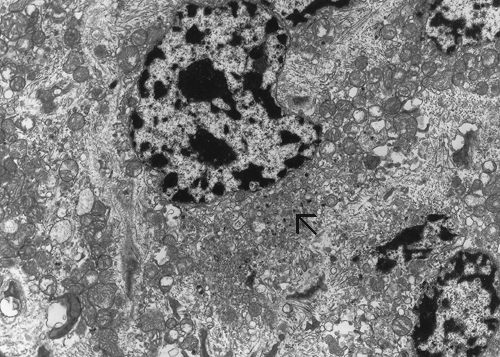

Electron microscopy: A substantial amount of mitochondria is present in the cytoplasm (Panel E and F). Admixed with the mitochondria are some small vesicles that typically have a dense core surrounded by a thin halo (Arrow in Panel E and F) and these are scare neuroendocrine (dense core) granules. Many of the mitochondria are also swollen (Panel G) and this feature may be a genuine feature or a result of mild artifact due to slight delay in fixation.

Under the electron microscope, the cytoplasm of oncocytoma is filled with mitochondria. A sparse number of neurosecretory granules (dense core granules) can also be seen. Both features are illustrated in our case.